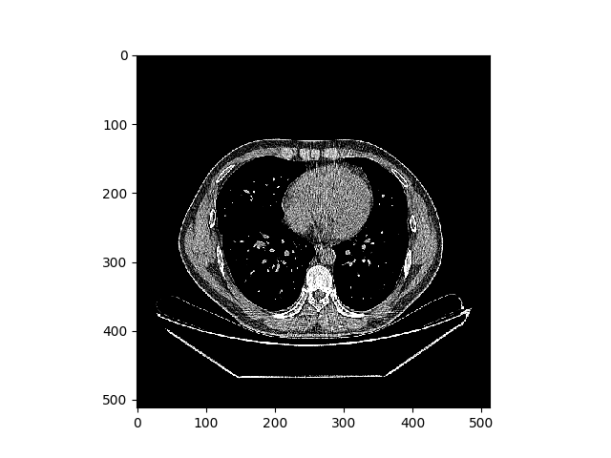

最后将图片转成的数组通过一些Hu像素的转化,使用点运算,将影像值转换为Hu值,然后通过调整vmax和vmin的属性,生成医学概念下的纵膈宽和肺部窗宽图像,对于肺部窗宽,调整之后会比之前呈现更好的亮度,而对于纵膈宽,调整之后会明显呈现一个关键部分突出的图像,如下所示

1210

图 7 肺部窗宽调整前后对比图

1110

图 8 纵膈宽调整前后对比图